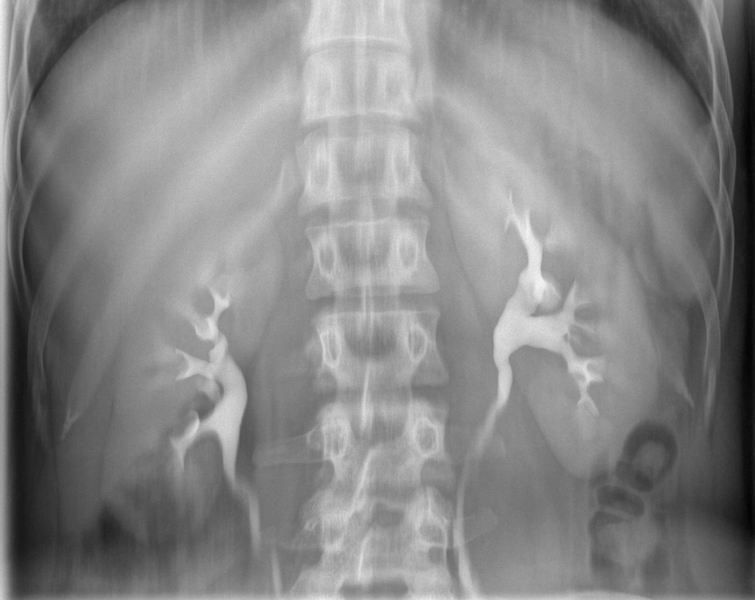

Hystero-salpingografie